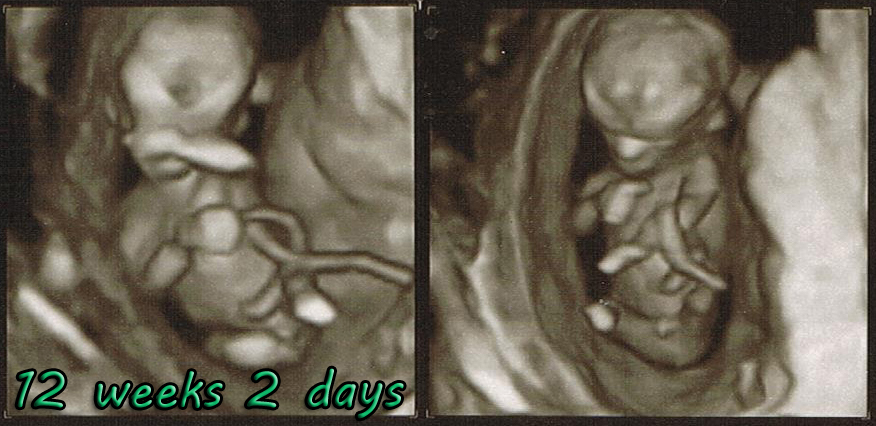

My doctor is guessing boy but I'd like to get some input from others. I'll find out for sure in 4 weeks!

I already have 3 daughters and 2 step-daughters but I'm scared to get my hopes up just yet lol

Attachment 14524

Attachment 14525